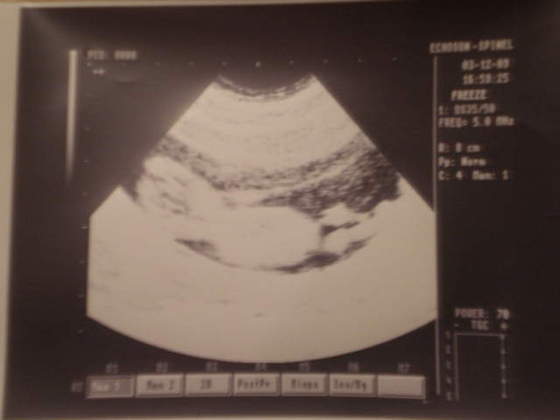

MOJE 8 CM SZCZĘŚCIA.

Płeć niestety nieokreślona, bo dziecko sobie w najlepsze spało

troszkę złej jakości, ale i tak piękne!!!!!ale uwierzcie mi na słowo na ekranie był/a prześliczne:-)